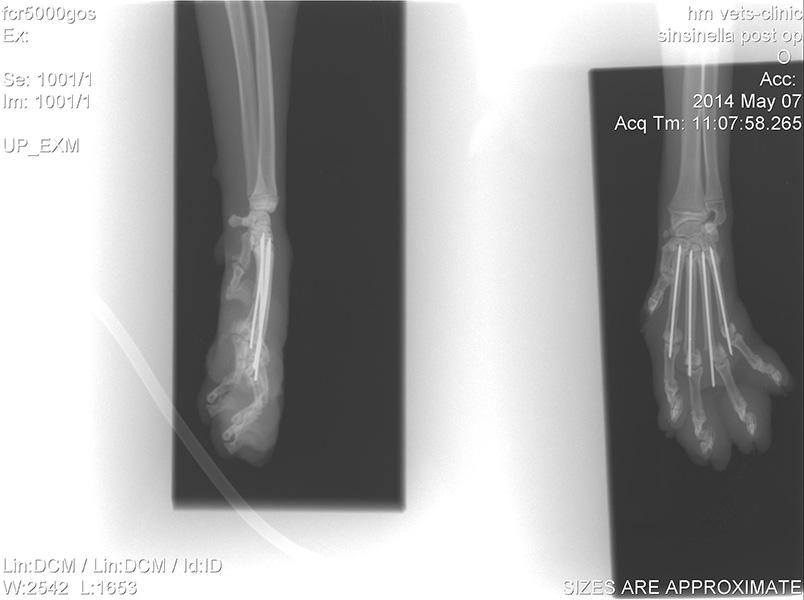

Ορθοπεδική

Ορθοπεδική

Το κτηνιατρείο hm vets αναλαμβάνει ψηφιακή ακτινογραφία, έλεγχο δυσπλασίας ισχίου, ορθοπεδική-νευροχειρουργική, χειρουργική μαλακών μορίων, οφθαλμολογία, εσωτερική παθολογία και εργαστηριακές εξετάσεις (αίματος, βιοχημικές, ανοσολογικές, ορμονολογικες, μοριακές και ιστοπαθολογικές).

Το κτηνιατρείο hm vets αναλαμβάνει ψηφιακή ακτινογραφία, έλεγχο δυσπλασίας ισχίου, ορθοπεδική-νευροχειρουργική, χειρουργική μαλακών μορίων, οφθαλμολογία, εσωτερική παθολογία και εργαστηριακές εξετάσεις (αίματος, βιοχημικές, ανοσολογικές, ορμονολογικες, μοριακές και ιστοπαθολογικές).